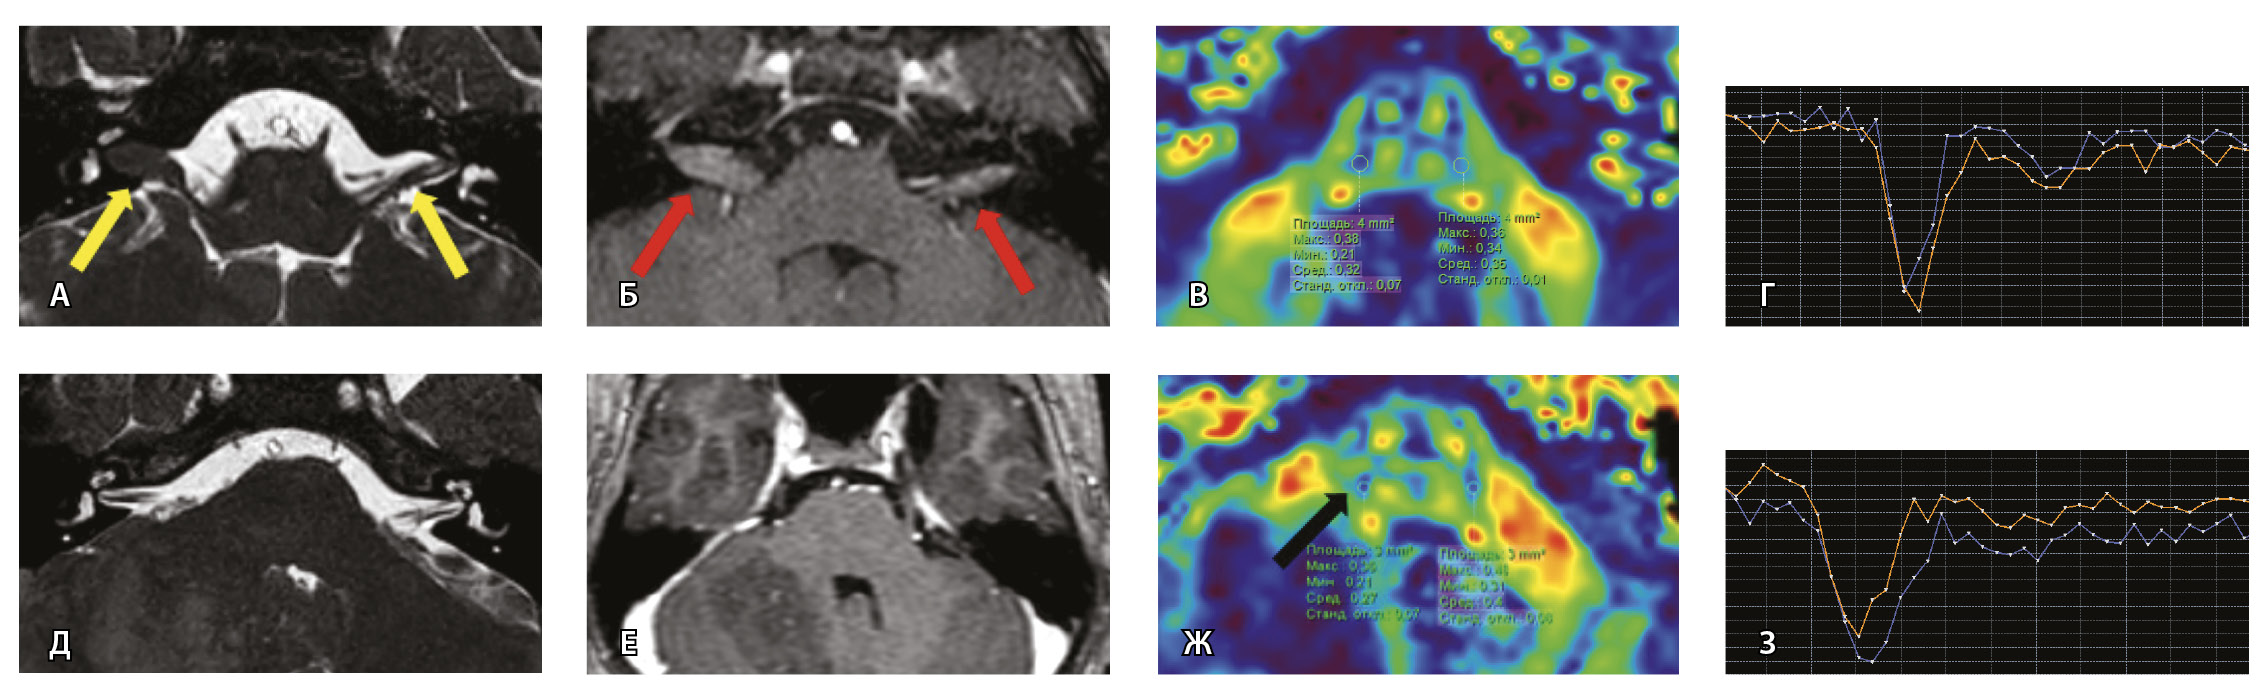

Далее представлены изображения МП-МРТ пациентов с НЛН и клинико-неврологическими данными, свидетельствующими в пользу ПБ. Для максимальной наглядности вышеуказанные клинические случаи (№ 2 и № 3) представлены в виде таблицы (рис. 7).

Рис. 7. Клиническое наблюдение 2, пациент 6 лет (А, Б, В, Г). Магнитно-резонансная томография (МРТ) головного мозга: А – прицельная T2-SSFP на область мосто-мозжечкового угла; Б – Т1-взвешенное изображение с контрастным усилением; В – диффузионно-тензорная МРТ (фракционная анизотропия, ФА); Г – Т2*-перфузия. На изображении T2-SSFP отмечается утолщение корешков лицевого, вестибуло-кохлеарного нервов во внутренних слуховых проходах (А, желтые стрелки) и интенсивное накопление ими контрастного вещества (Б, красные стрелки). На уровне моторных ядер лицевых нервов в заднем отделе варолиевого моста значения ФА симметричны (В), признаков гипо-/гиперперфузии не выявлено (Г).

Клиническое наблюдение 3, пациент 13 лет (Д, Е, Ж, З). МРТ головного мозга: Д – прицельная T2-SSFP на область мосто-мозжечкового угла; Е – Т1-взвешенное изображение с контрастным усилением; Ж – диффузионно-тензорная МРТ (ФА); З – Т2*-перфузия. На изображении T2-SSFP патологические изменения на уровне прохождения лицевых нервов во внутренних слуховых проходах не определяются (Д). В медиальном отделе правого полушария мозжечка определяется объемное образование, компримирующее стенку IV желудочка и задний отдел варолиевого моста без признаков васкуляризации (Е). На уровне моторных ядер лицевого нерва в заднем отделе варолиевого моста на изображениях ФА на стороне поражения отмечается минимальное уменьшение показателя ФА до 0,27 (Ж, черная стрелка) и признаки гипоперфузии (З, оранжевый график) по сравнению с контралатеральной стороной (З, синий график)

При этом в клиническом наблюдении № 2 из анамнеза жизни известен ранее установленный диагноз лимфобластного лейкоза в стадии ремиссии. В клиническом наблюдении № 3 значимых анамнестических сведений и данных в пользу атипичного течения ПБ получено не было.

Таким образом, при помощи информации, полученной при проведении МП-МРТ, в обоих случаях был установлен симптоматический характер НЛН, обусловленный развитием неопластических процессов. Оба пациента были направлены в профильные хирургические стационары для проведения дальнейшего лечения.